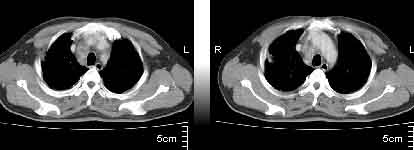

该病例我的诊断意见:右肺上叶周围型肺癌伴纵隔和右肺门淋巴结增大和右肺上叶阻塞性肺炎{病灶周围致密影以近肺门侧明显!}。右侧少量胸腔积液。

一. 1)症状有无发热及慢性过程.2)化验室检查?3)有无tb接触史?二.右肺上叶见片团状影,边界欠清,外侧方见一结节状软组织影,密度欠均匀,内可见低密度坏死区.周围强化明显,肺内见纤维索条影,局部胸膜增厚,但无明确胸膜凹陷.上叶支气管壁增厚,肺门及纵隔淋巴结增大.右侧胸腔少量积液.诊断意见:1右肺上叶慢性感染性疾病(肺tb?)伴肺门,纵隔淋巴结大.右胸少量积液.右肺上叶结节影多为tb球?2右肺上叶周围型肺ca伴肺门,纵隔淋巴结转移待排.右肺上叶炎变(肺门及纵隔淋巴结压迫).右胸少量积液.等待随返结果.

中轴间质增粗可以用癌局部淋巴侵润解释。近肺门侧片影用肺门淋巴结增大解释并压迫支气管引起近端炎症?